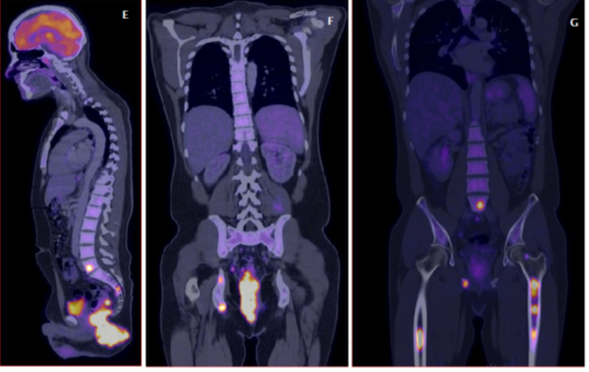

Positron Emission Tomography (PET-CT) was performed with evidence of tumor hypermetabolic activity at the rectal level (SUVmax 70.2), presacral and pararectal lymph nodes (SUVmax 46.6), inguinal (SUVmax 52.3), ischium, ischiopubic ramus (SUVmax 43.3), Liver (SUVmax 8.4). (Figure 2 &3)

Figure 2 E: Sagittal reconstruction of PET-CT with evidence of tumor hypermetabolic activity at the rectal level (SUVmax 70.2) FIGURES F and G: PET-CT coronal reconstruction with evidence of tumor metabolic activity at the rectal level (SUVmax of 70.2), ischium and femurs (SUVmax of 43.3).

Figure 3 Axial reconstruction with evidence of tumor hypermetabolic activity at the rectal level (SUVmax 70.2), presacral and pararectal lymphadenopathies (SUVmax 46.6), inguinal (SUVmax 52.3).